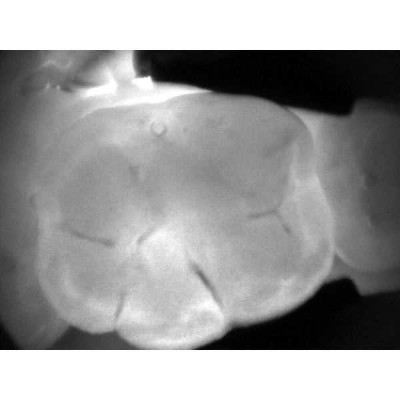

Весь секрет заключается в технологии DIFOTI за счет генерируемого прибором трансилюминационного (трансиллюминация - яркое сквозное освещение) лазерного излучения в нерентгеновском диапазоне волн. Если объяснять это простым языком, то это излучение, занимающее диапазон между видимым светом и рентгеновским диапазоном, которое проходит сквозь твердые ткани зуба, при этом области, не пропускающие свет (например, области кариозного поражения) отображаются в виде затемненных на общем фоне участков.

Рентгенограммы и снимки, полученные с помощью KaVo DIAGNOcam, относятся к методам диагностики, прекрасно дополняющим друг друга. С помощью рентгенологической диагностики Вы в дальнейшем сможете беспрепятственно проверить и дополнить данные KaVo DIAGNOcam, исключив часть рентгеновского излучения для пациента. На снимках отчетливо визуализируются структуры коронковой части зуба, располагающиеся выше уровня десневого края. Таким образом, становится возможным раннее распознавание кариеса и проведение профилактического, малоинвазивного лечения. Ваши пациенты будут в восторге!

- Выявление трещин эмали без применения стоматологического микроскопа.

- Обнаружение кариеса на раннем этапе развития.